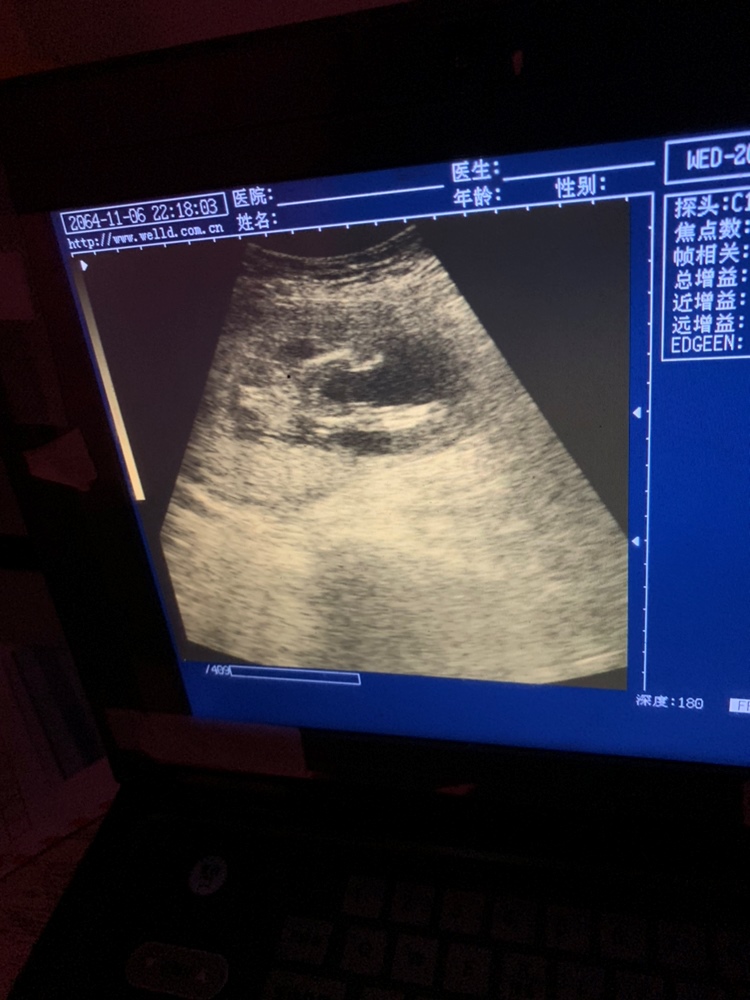

孕19周+1天

女翻男,多,容易看错。男翻女少

我也是16周查是女宝,今天四维后再查成弟弟了,不敢相信自己的耳朵,现在都没接受过来,女儿梦破碎了

煙火🔥[帖主]:不会吧,这个还会变的?

💭 小铭同学:不会变,可能是当时体位,机器,医生技术问题没看准

煙火🔥[帖主]:我想也是一般胎儿三个月左右就发育成形了,有经验技术好的医生应该不会看错